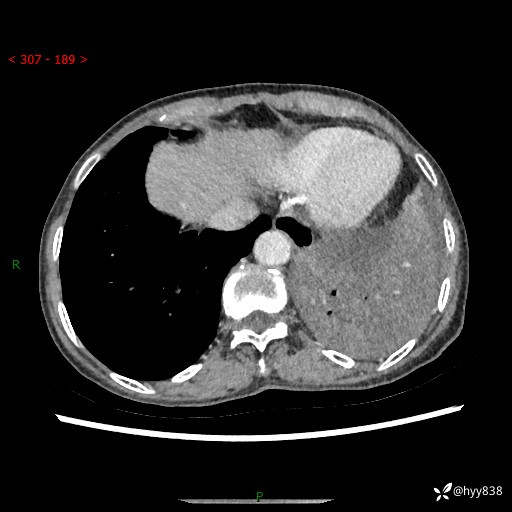

胸部CT平扫+增强